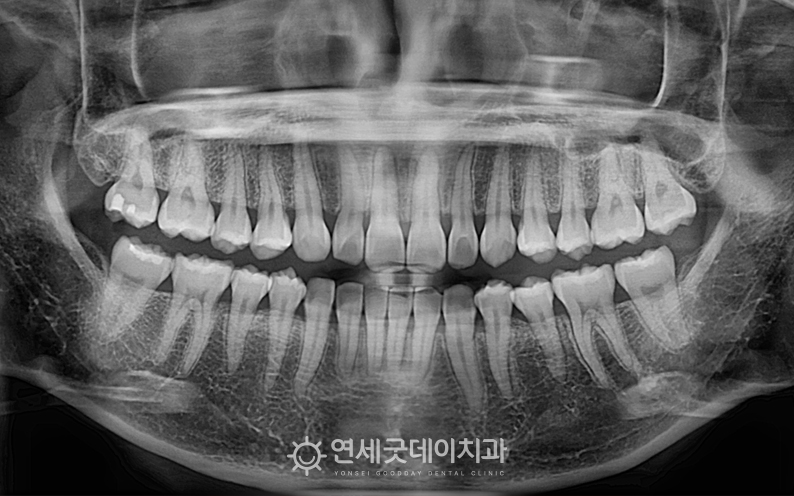

▲ 치료 전 엑스레이 (촬영시기 : 2022년 10월) 엑스레이를 보면 35번 치아가

하지만 #35 치아가 쓰러지면서 또 한 가지 주의 깊게 살펴볼 부분은 ‘과개교합’입니다. ▲ 치료전 안모 (촬영시기 : 2022년 10월) 환자분은 과개교합, 쓰러진 치아로 인한 인접치의 정출 따라서 부분교정의 한계점에 대해 충분히 설명드린 후 ▲ 과개교합 교정 후 엑스레이 (촬영시기 : 2024년 3월) 약 1년 6개월의 인비절라인 교정이 마무리되었습니다. 기울어진 치아는 정상적인 위치로 올바르게 세워졌으며 ▲ 과개교합 교정 종결 (촬영시기 : 2024년 3월) 윗니의 높이와 각도가 개선되면서 아랫니가 정상적으로 드러나고, ▲ 치료 후 안모 (촬영시기 : 2024년 3월) 웃을 때마다 과도하게 드러났던 거미스마일도 ▲ 치료전후 비교 (촬영시기 : 2022년 10월 / 2024년 3월) 과개교합은 턱관절 불편감이나 저작 불편으로 이어질 수 있어 과개교합을 교정함으로써 증상을 완화하고 그동안 치료 받으시느라 고생 많으셨습니다. ^^ ※ 모든 사진은 본인의 동의를 얻어 동일조건에서 촬영하였으며 |